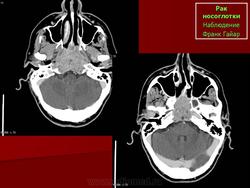

ЛОР. Онк. Рак носоглотки. +

Рак носоглотки